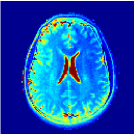

Ground truth (T1, T2, PD) anatomical maps acquired by the MAGIC gold standard [21]

T1 (sec) T1 error T2 (sec) T2 error PD (a.u.) PD error

Table 1 and Figure 2 compare the performances of the MRF baselines against our proposed PGD-Net using and 5 recurrent iterations. We also include inference results using the proposed encoder alone , without proximal iterations. Reconstruction performances were measured by the Normalised RMSE , MAE , Structural Similarity Index Metric (SSIM) [28], the required storage for the MRF dictionary (in DM methods) or the networks, and the algorithm runtimes averaged over the test image slices.

The non-iterative FGM results in incorrect maps due to the severe under-sampling artefacts. The model-based BLIP iterations improve this, however, due to lacking spatial regularisation, BLIP has limited accuracy and cannot fully remove aliasing artefacts (e.g. see T2 maps in Figure 2) despite 20 iterations and very long runtime. In contrast, all deep learning methods outperform BLIP not only in accuracy but also in having 2 to 3 orders of magnitude faster reconstruction times—an important advantage of the learning-based methods. The proposed PGD-Net consistently outperforms all baselines, including DM and learning-based methods, over all defined accuracy metrics. This is achieved due to learning an effective spatiotemporal model (only) for the proximal operator i.e. the and Bloch networks, directly incorporating the physical acquisition model H into the recurrent iterations to avoid over-parameterisation of the overall inference model, as well as enforcing reconstructions to be consistent with the Bloch dynamics and the k-space data through the multi-term training loss (6). The MRFCNN and SCQ over-parametrise the inference by 1 and 3 orders of magnitude larger model sizes (the SCQ requires larger memory than DM) and are unable to achieve PGD-Net’s accuracy e.g. see the corresponding over-smoothed T2 maps in Fig. 2. Finally, we observe that despite having roughly the same model size (storage), the encoder alone predictions are not as accurate as the results of the PGD-Net’s recurrent iterations. By increasing the number of iterations we observe that the PGD-Net’s accuracy consistently improves despite having an acceptable longer inference time.